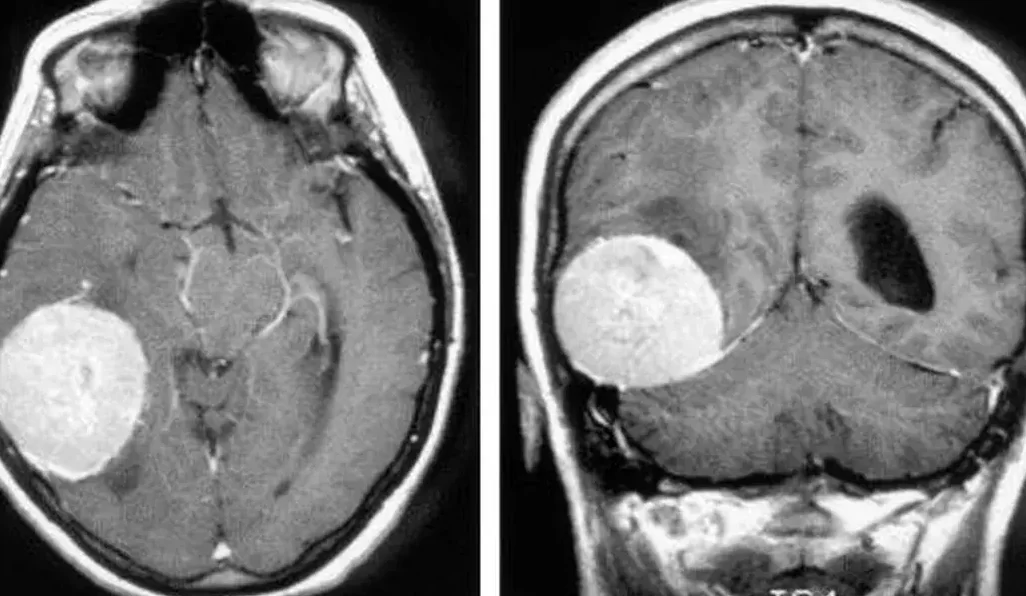

Si experimentas uno o más de estos síntomas, es fundamental acudir a un neurólogo para realizar una evaluación exhaustiva. El diagnóstico de un tumor cerebral se realiza a través de la realización de exámenes específicos, como una resonancia magnética o una tomografía computarizada. Estos exámenes permiten evaluar el tamaño y las características de las células tumorales, lo que ayuda al médico a determinar el mejor tratamiento.

El diagnóstico de un tumor cerebral se realiza a través de exámenes específicos, como una resonancia magnética o una tomografía computarizada. Estos exámenes permiten evaluar el tamaño y las características de las células tumorales.